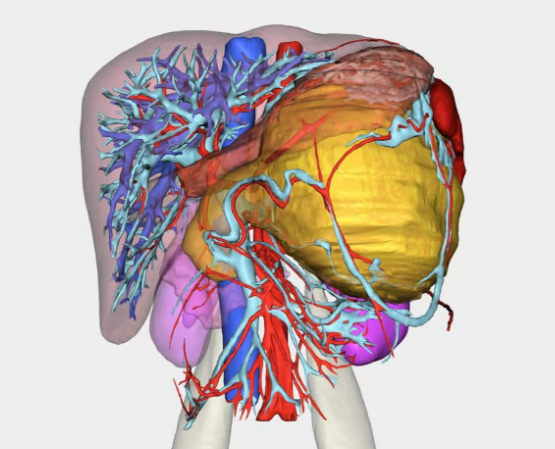

田毅峰教授、陈实教授经过数字成像智能评估后,准确分析并制定出微创下切除肿瘤的最便捷路径,为赵某实施机器人辅助胰体尾脾切除术,术中借助机器人高清的三维视野、灵活的机械臂、精细操作,在狭小的空间中最终完整切除肿瘤,成功实现微创手术,术后恢复良好,患者腹部只留下4cm的隐匿伤口,做到“大切除、小伤口”,充分体现了机器人智能系统在胰腺外科中的极致优势。

数字成像智能评估手术路径

术前术后对比图